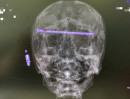

В городской больнице № 1 Нижнего Тагила нейрохирурги провели сложную операцию по извлечению 15-сантиметрового гвоздя из черепа 78-летнего пациента,...